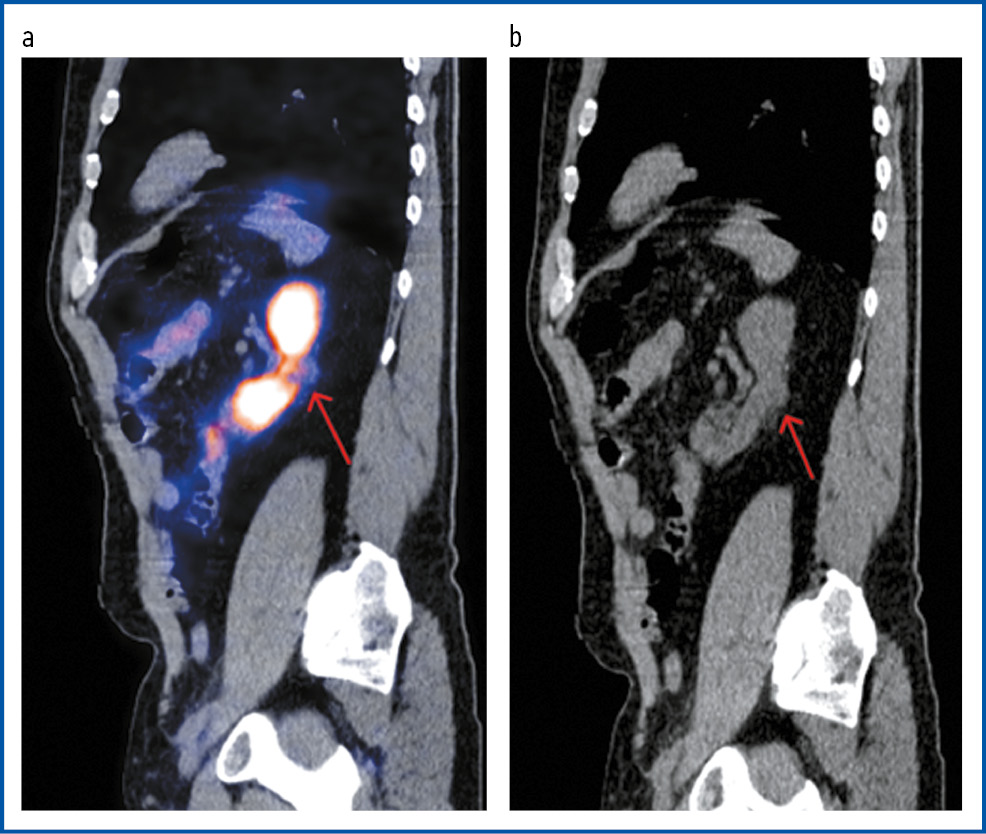

Рис. 6. Пациент А., 72 года. ПЭТ/КТ с 18F-PSMA. В сагиттальной проекции ПЭТ/КТ (а) и КТ-исследовании (b) в верхнем сегменте левой почки имеется опухолевое образование с гиперфиксацией РФП, SUVmax 7,78, размерами 25 × 17 мм.

Fig. 6. Patient A., 72 years old. PET/CT with 18F-PSMA. In the sagittal view of PET/CT imaging and CT, a tumor mass was detected in the upper segment of the left kidney with RPA hyper uptake, SUVmax 7.78, 25 × 17 mm.